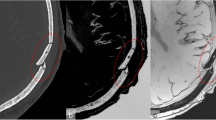

The models were randomly placed onto a table and numbered from 1 to 12 for viewing by study participants, who were recruited from the local research and clinical environment of the principal investigator (A.C.), in South Africa. Representative MR images and the corresponding 3-D printed models of three cases are shown in Figs. 1, 2, and 3.

Images of an 11-year-6-month-old girl presenting with cerebral palsy. a, b Axial (a) and sagittal (b) T1-weighted magnetic resonance images show localized perirolandic atrophy and signal change (red arrows) and lentiform separation of the cerebral hemisphere (white arrow). c Vertex (c, d) and lateral oblique (d) 3-dimensional printed models with accurate depiction of the lentiform separation (white arrow) and perirolandic atrophy (black arrows)